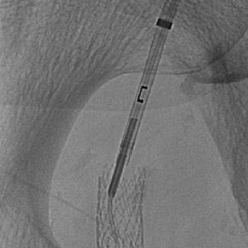

GoBack® CATHETER

Your Crossing Solution for Tough CTO’s

• Unique peripheral solution for difficult lower extremities occlusions including BTK and in-stent restenosis

• Considered the “Swiss Army Knife” for CTO’s, GoBack can be used for intraluminal crossing and guidewire support

• Intra-luminal CTO crossing

• Heavily calcified in-stent restenosis